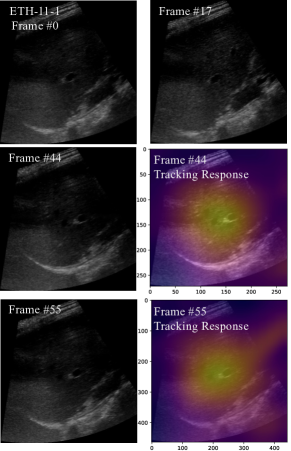

Refer to caption

Figure S1: Qualitative deformation comparison of the proposed LSDM based on different deformation module combinations. We select one representative dataset entriy to demonstrate superior LSDM deformation performance. For each entry, we show the fixed template at frame 0 (top-left), selected target frame (bottom-left), warped images based on different deformation combination (bottom row) and visualization of determinant of jacobian matrix from a different displacement field (top row), where red indicates the determinant of jacobian is greater than 1 and blue indicates the value of the determinant of jacobian is negative. We can observe a progressive smooth setting with proposed long-short deformation and EMMA module. Together with DPN, the LSDM learns to generate the optimal deformation for downstream tasks like tracking. Best viewed in color.